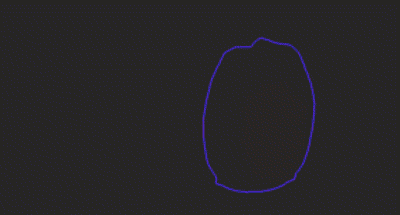

DVSM: a tool for contouring and medical image visualization